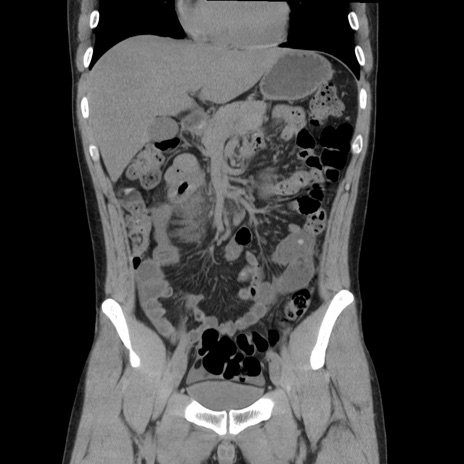

症例36(冠状断像)

【症例】20歳代 男性

【主訴】心窩部痛

【現病歴】今朝より上腹部痛あり。一旦軽快していたが再度出現したため救急要請。昨日夕に白身の魚を含む刺身を食べた。

【身体所見】BP 136/89mmHg、HR 74/min、BT 37.0℃、腹部:膨満、軟、心窩部に圧痛あり。反跳痛なし、筋性防御なし、腸雑音やや亢進あり。

【データ】WBC 17700、CRP 0.48